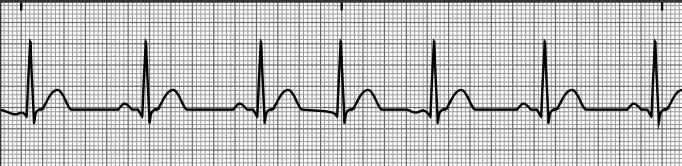

sinus bradycardia

normal sinus rhythm

sinus tachycardia